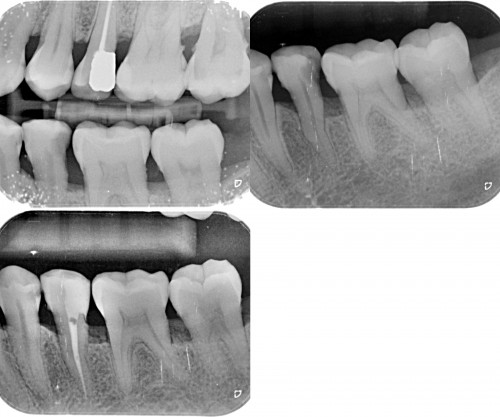

Nice cases. For the maxillary molar, did you use a saddle matrix on the second stage amalgam?

Dr. Miglani,

You demonstrate some very accomplished skills…..these are not easy restorations to do well. The enod also looks very carefully done. Keep it up!

Great execution Revathi both on the restorative and the endodontic aspects ,especially in hard to isolate areas.